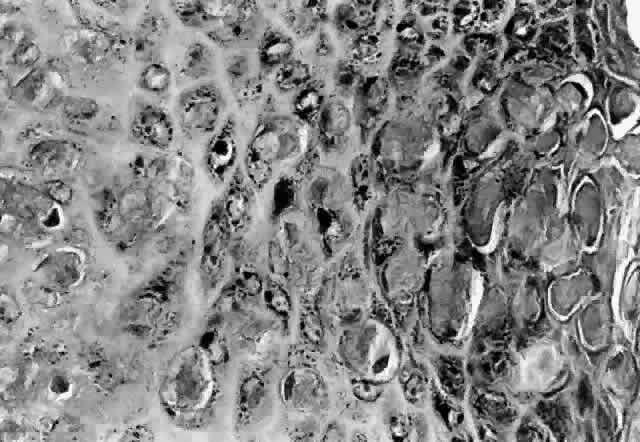

Molluscum contagiosum is a papule with lobular downgrowth of epithelium into the dermis and a central “crater” on the surface (Fig. 11). The epithelium and infected cells demonstrate hyperplasia. Basal cells divide more rapidly (6.1 day turnover decreasing to 3.4 days) and infected cells show more rapid migration through the epithelium as well as cessation of host DNA transcription.121,122 Each lobule demonstrates a progression from base to top. The malpighian cells contain eosinophilic elementary bodies (Fig. 12). These coalesce to form a hyaline molluscum body (HendersonPaterson body).123 The cytoplasmic molluscum bodies increase in size until they distort and displace the nucleus, sometimes becoming larger than the original host cell (Fig. 13). At the top of the lobule in the granular cell layer, the Henderson-Paterson inclusion body changes from eosinophilic to basophilic. When the overlying stratum corneum loses its integrity, the crater is formed (see Fig. 10). Microdissection revealed124 and scanning electron microscopy confirmed125 the presence of a sac surrounding the viral inclusion body within each cell, which has been speculated to provide an immunologically sheltered site for viral reproduction.

Fig. 12. Molluscum contagiosum, histology. Evolution of molluscum bodies from base (left) to center of lobule (right). (Original magnification × 200)

Fig. 13. Molluscum contagiosum, histology. High-power view of transition zone. Molluscum bodies are apparent (right). Note the dark, displaced nuclei. (Original magnification × 400)